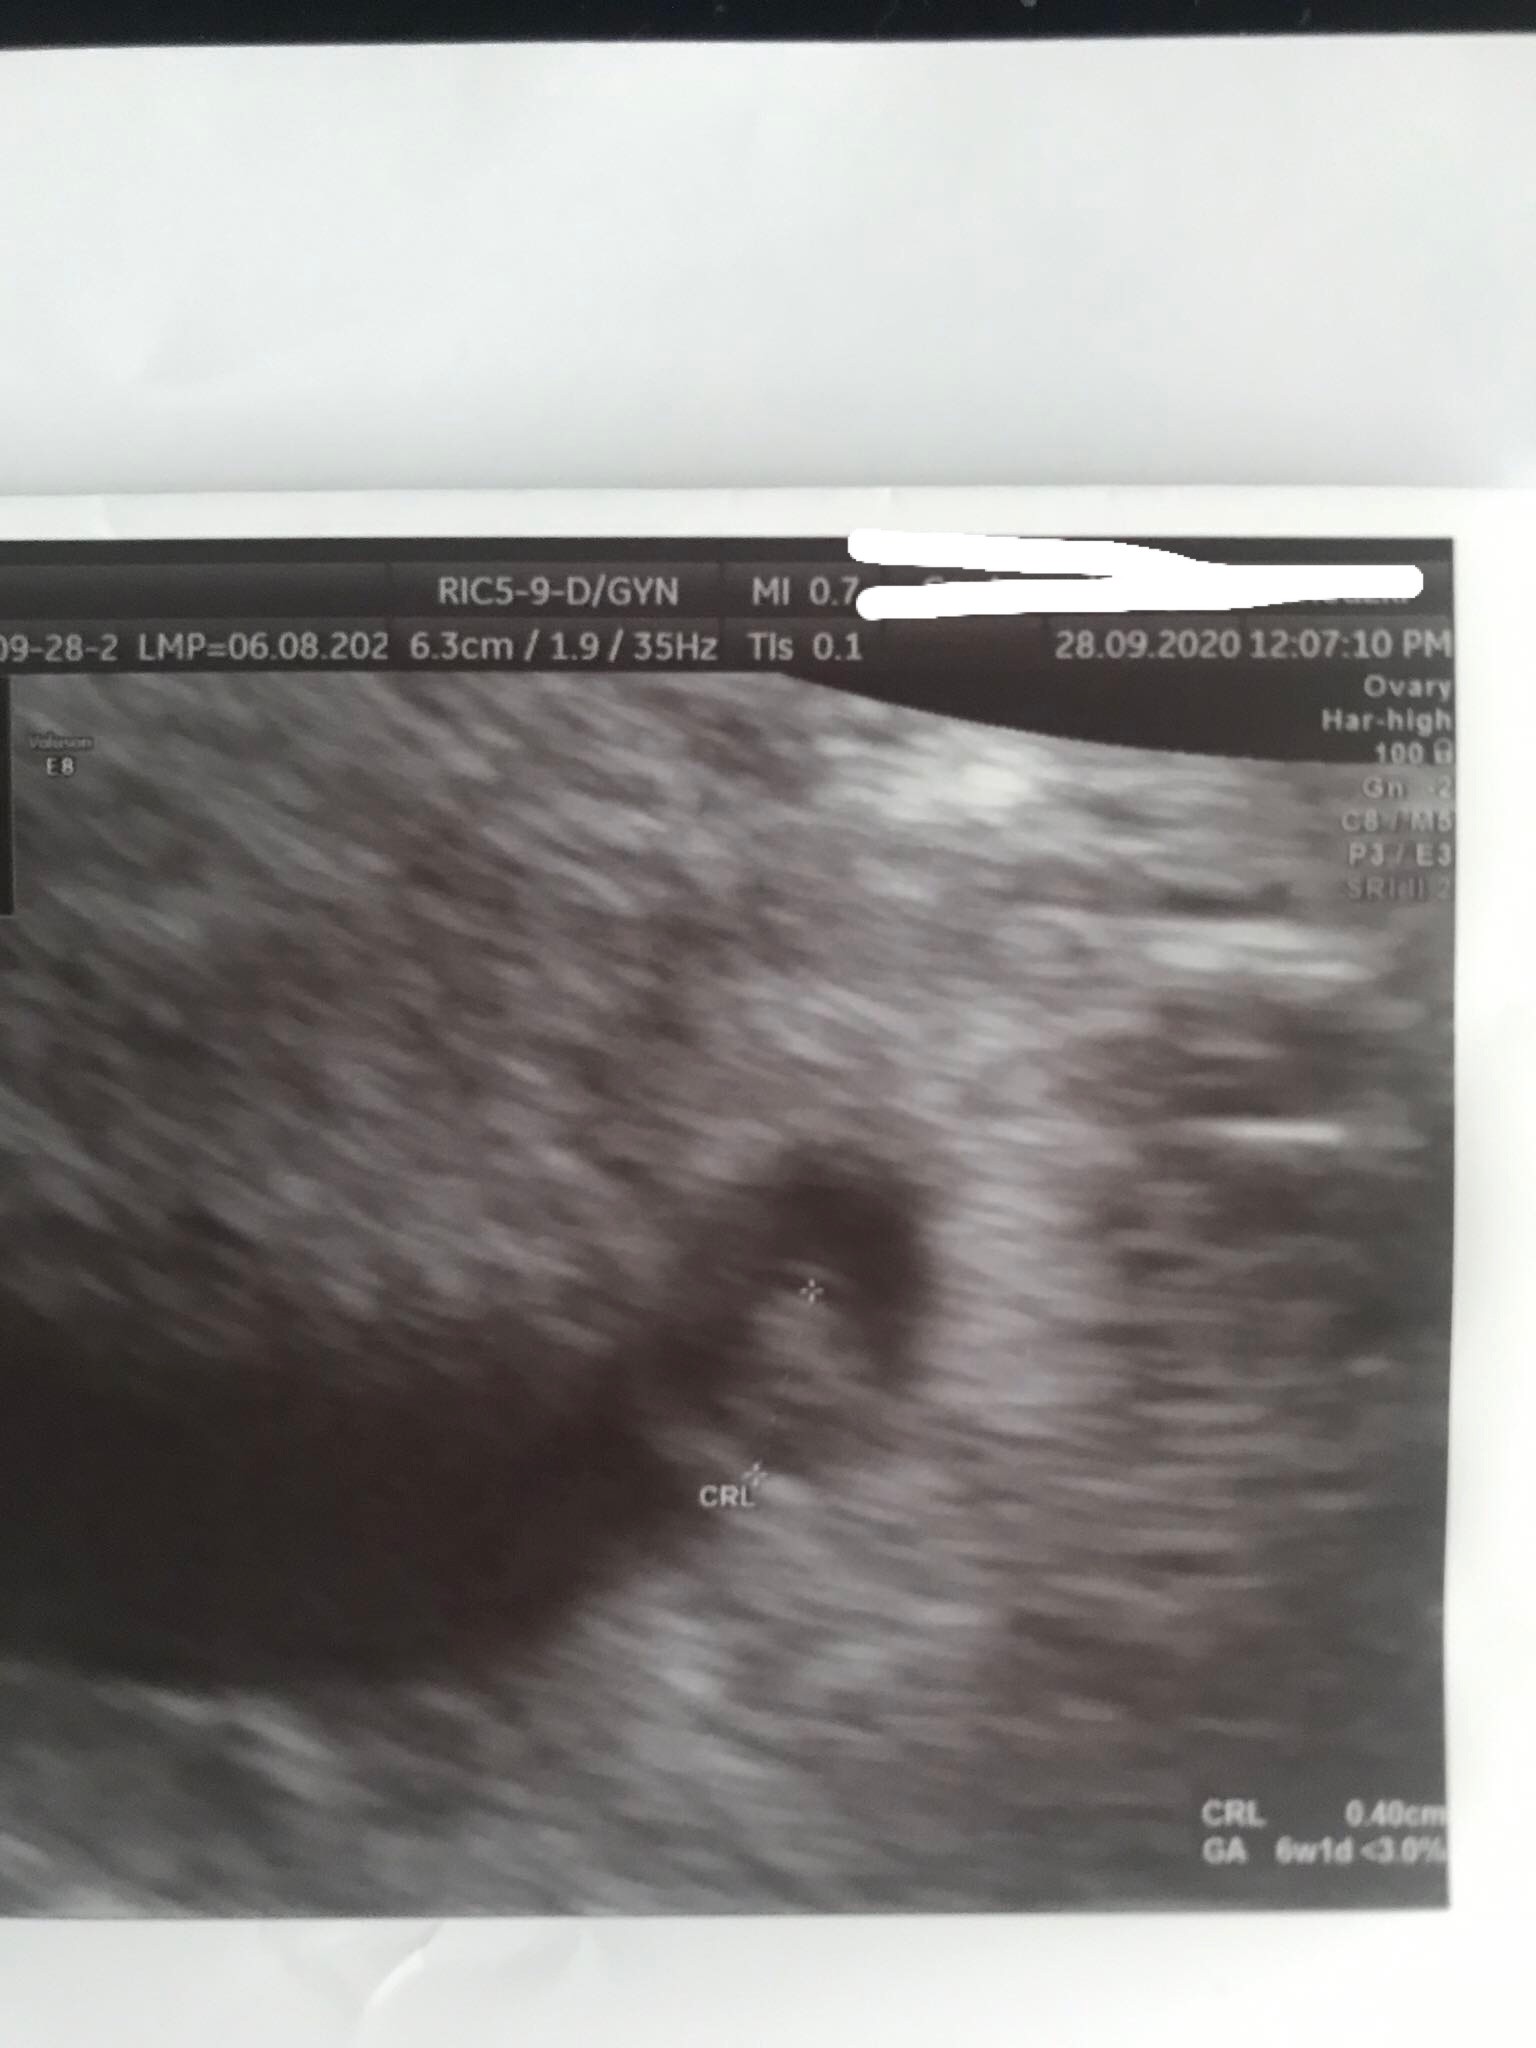

Super zdjęcie usgHej już po wizycie. 8+0, bąbel ma już 1,66cm, serduszko 168/min ❤ I już ma raczki i nóżki, słodko sobie machaNa zdjęciu nie widać za bardzo kończyn, ale na szczęście wszystko w porządku. A miałam jakieś złe przeczucia niepotrzebnie